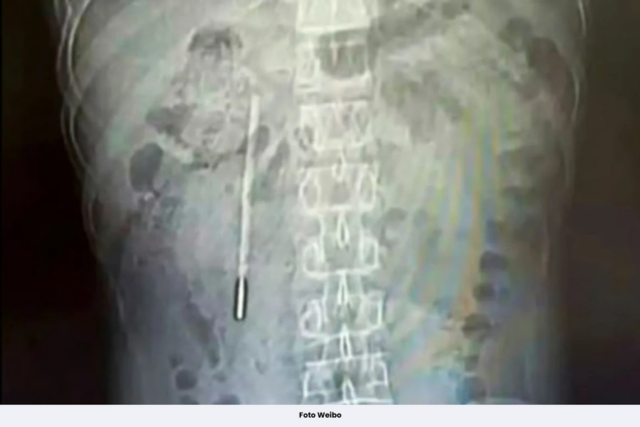

Imbasan mendedahkan objek asing di duodenumnya (bahagian pertama usus kecil vertebrata, yang disyaki oleh doktor sebagai termometer merkuri.

Oleh kerana hujung termometer menekan terus ke dinding usus, ia menimbulkan risiko perforasi dan pendarahan dalaman yang teruk.

Pakar bedah mengeluarkan objek itu hanya dalam 20 minit.

Pembedahan itu sangat teliti kerana termometer berada dalam badan untuk tempoh lama dan terletak berhampiran dengan saluran hempedu Wang, yang menimbulkan risiko yang ketara merosakkan dinding usus.

Termometer yang diambil masih utuh tetapi tanda ukurannya sudah pudar.